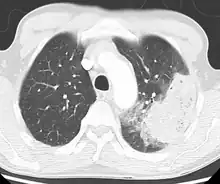

A chest radiograph is frequently used in diagnosis.[20] In people with mild disease, imaging is needed only in those with potential complications, those not having improved with treatment, or those in which the cause is uncertain.[20][60] If a person is sufficiently sick to require hospitalization, a chest radiograph is recommended.[60] Findings do not always match the severity of disease and do not reliably separate between bacterial infection and viral infection.[20]

X-ray presentations of pneumonia may be classified as lobar pneumonia, bronchopneumonia, lobular pneumonia, and interstitial pneumonia.[66] Bacterial, community-acquired pneumonia classically show lung consolidation of one lung segmental lobe, which is known as lobar pneumonia.[34] However, findings may vary, and other patterns are common in other types of pneumonia.[34] Aspiration pneumonia may present with bilateral opacities primarily in the bases of the lungs and on the right side.[34] Radiographs of viral pneumonia may appear normal, appear hyper-inflated, have bilateral patchy areas, or present similar to bacterial pneumonia with lobar consolidation.[34] Radiologic findings may not be present in the early stages of the disease, especially in the presence of dehydration, or may be difficult to interpret in the obese or those with a history of lung disease.[21] Complications such as pleural effusion may also be found on chest radiographs. Laterolateral chest radiograph can increase the diagnostic accuracy of lung consolidation and pleural effusion.[33]

A CT scan can give additional information in indeterminate cases.[34] CT scans can also provide more details in those with an unclear chest radiograph (for example occult pneumonia in chronic obstructive pulmonary disease) and is able to exclude pulmonary embolism and fungal pneumonia and detecting lung abscess in those who are not responding to treatments.[33] However, CT scan is more expensive, has a higher dose of radiation, and cannot be done at bedside.[33]